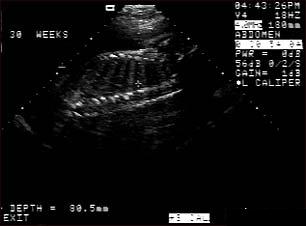

Ecografia fetala